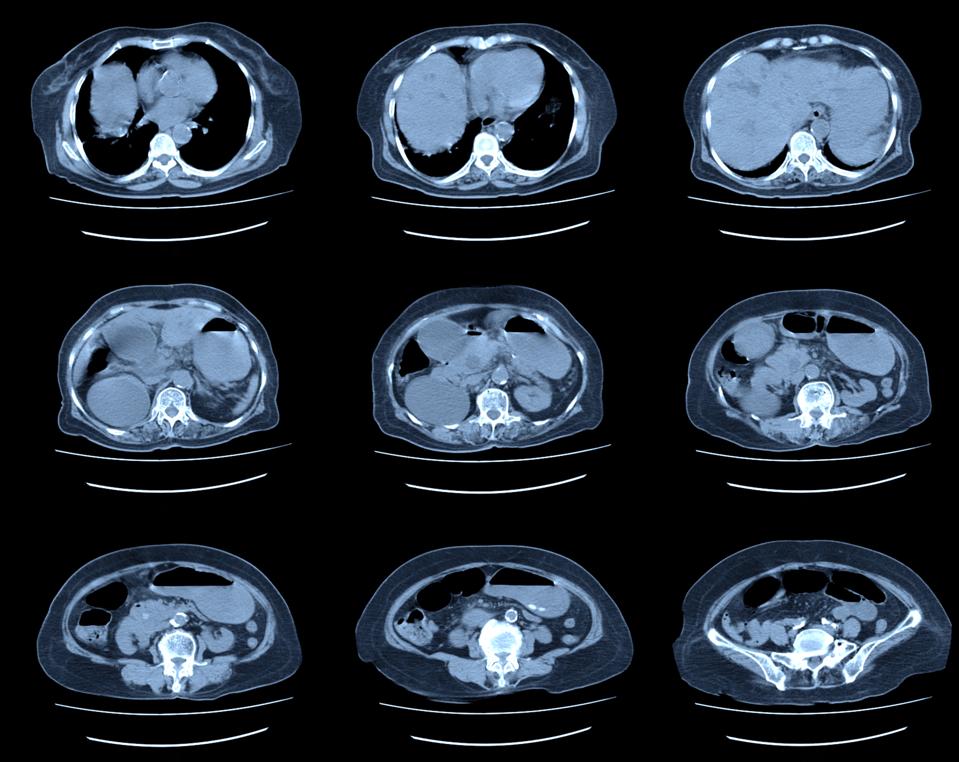

Let’s start with some facts about kidney cancer. The number of people being diagnosed with kidney cancer is rising dramatically in the United States. Just between 2001 and 2010, the rate of such diagnoses grew almost 20%. Some of that increase is due to the aging of the American population, and some to the increased rate of obesity. But much of it results from the increasing number of people receiving CT scans in the United States, for one reason or another, with those scans revealing suspicious growth in their kidneys.